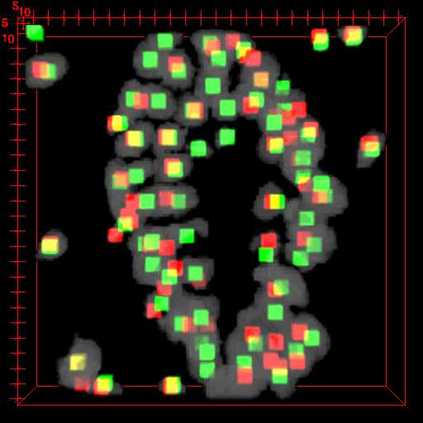

Robust and accurate nuclei centroid detection is important for the understanding of biological structures in fluorescence microscopy images. Existing automated nuclei localization methods face three main challenges: (1) Most of object detection methods work only on 2D images and are difficult to extend to 3D volumes; (2) Segmentation-based models can be used on 3D volumes but it is computational expensive for large microscopy volumes and they have difficulty distinguishing different instances of objects; (3) Hand annotated ground truth is limited for 3D microscopy volumes. To address these issues, we present a scalable approach for nuclei centroid detection of 3D microscopy volumes. We describe the RCNN-SliceNet to detect 2D nuclei centroids for each slice of the volume from different directions and 3D agglomerative hierarchical clustering (AHC) is used to estimate the 3D centroids of nuclei in a volume. The model was trained with the synthetic microscopy data generated using Spatially Constrained Cycle-Consistent Adversarial Networks (SpCycleGAN) and tested on different types of real 3D microscopy data. Extensive experimental results demonstrate that our proposed method can accurately count and detect the nuclei centroids in a 3D microscopy volume.